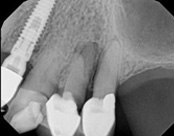

The patient presented with mild pain, a cavity, and a broken filling was evident. After performing diagnostic testing, the diagnosis was: irreversible pulpitis, symptomatic periradicular periodontitis. Root canal therapy was done and the tooth healed well and is still functioning.